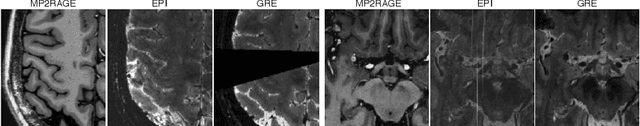

Abstract:The automated detection of cortical lesions (CLs) in patients with multiple sclerosis (MS) is a challenging task that, despite its clinical relevance, has received very little attention. Accurate detection of the small and scarce lesions requires specialized sequences and high or ultra-high field MRI. For supervised training based on multimodal structural MRI at 7T, two experts generated ground truth segmentation masks of 60 patients with 2014 CLs. We implemented a simplified 3D U-Net with three resolution levels (3D U-Net-). By increasing the complexity of the task (adding brain tissue segmentation), while randomly dropping input channels during training, we improved the performance compared to the baseline. Considering a minimum lesion size of 0.75 {\mu}L, we achieved a lesion-wise cortical lesion detection rate of 67% and a false positive rate of 42%. However, 393 (24%) of the lesions reported as false positives were post-hoc confirmed as potential or definite lesions by an expert. This indicates the potential of the proposed method to support experts in the tedious process of CL manual segmentation.